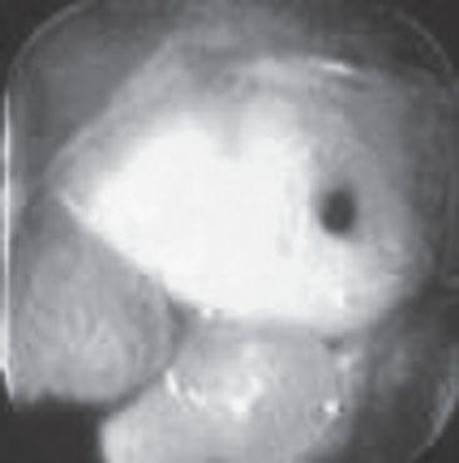

In a patient with melena but a normal hematocrit, the lesion below was found on upper endoscopy. Based on its appearance, what is the approximate risk of rebleeding from this lesion?

Figure 1-3 See also color plate.

The risk of rebleeding in an ulcer with a flat pigmented spot is about 10%.